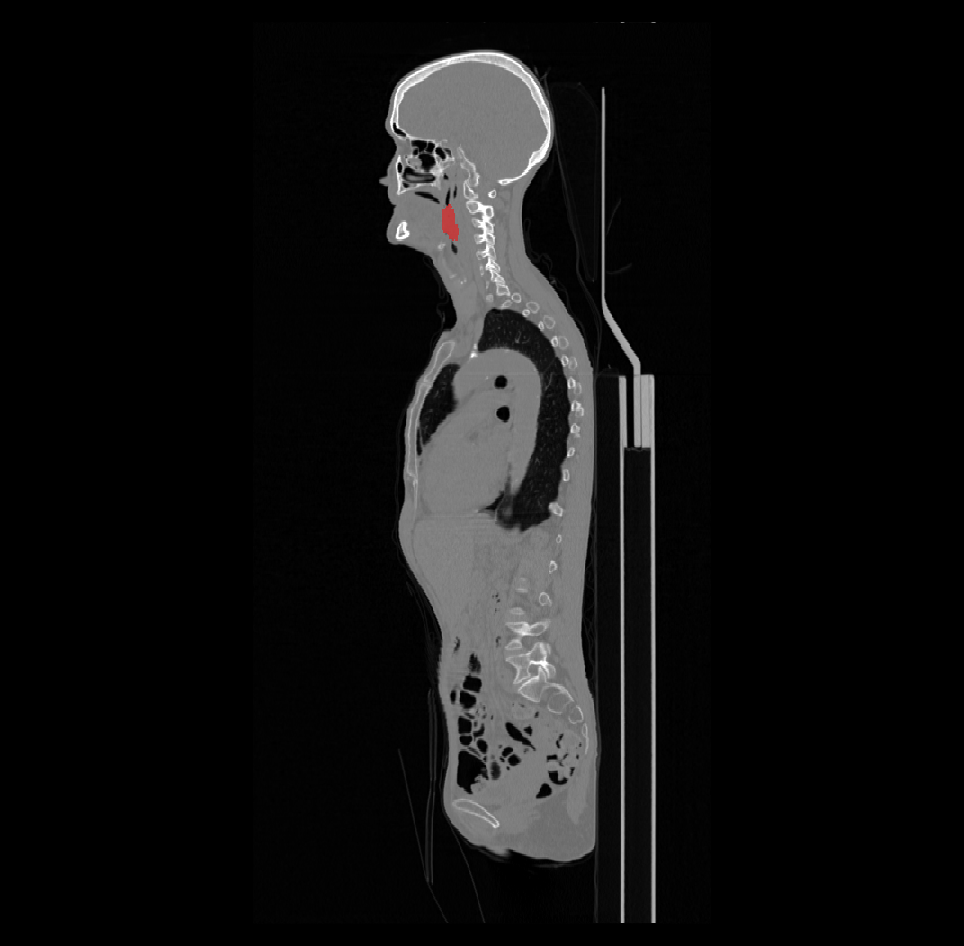

The training dataset with the ground truth labels consists of 524 cases with average 3D CT size of 512x512x200 voxels at 0.98x0.98x3 mm average resolution, and with average 3D PET size of 200x200x200 voxels at 4x4x4 mm. The CT and PET image pairs where rigidly aligned to a common origin, but remain at different sizes and resolutions. Many cases provided were almost a full body CT/PET pairs. This provides both computational and algorithmic challenge, since the imaging region is as large as 500x500x1000 mm of the body anatomy, whereas the tumor region covers less then 5% of the input images.

The ground truth labels usually include a single mass of the primary tumor (but in some cases it was absent completely or had two components), and several connected components of the annotated lymph nodes. An example case of CT and the corresponding PET image with ground-truth overlays is shown in Figures 1 and 2.